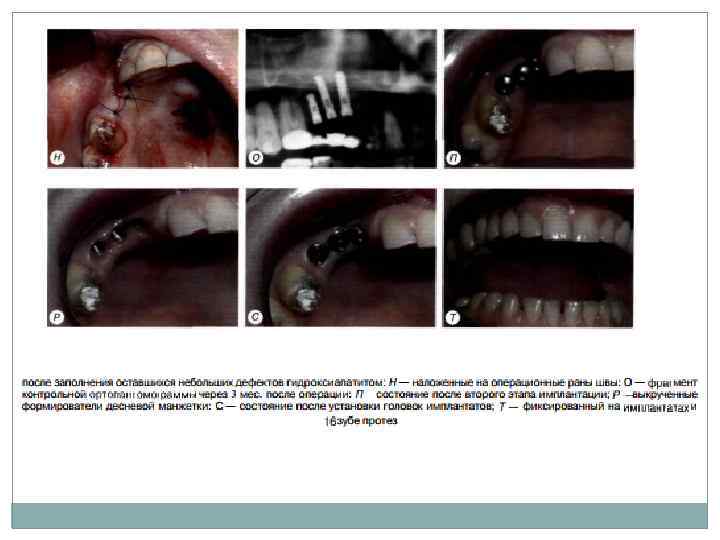

Второй этап операции проводят через 2 3 мес. после установки внутрикостных элемен тов. Под местной инфи. ьтрапионной анестези ей при помощи зонда определяют расположение внутрикостных элементов под слизистой обо лочкой. Если из за значительной ее толщины или нарастания костной ткани на внутрикостную часть и заглушку (рис. 11 4) определить расположение имплантата зондом невозможно, необходимо произвести разрез слизистой обо лочки длиной до 10 мм в месте, где должен на ходиться внутрикостный элемент. Второй этап двухэтапной методики имплантации

Второй этап двухэтапной методики имплантации Затем, от слаивая слизистую оболочку определяют рас положение имплантата визуально. Иссечение слизистой оболочки над внутрикостным эле ментом производят перфоратором и удаляют иссеченный участок (рис. 11 5). Выкручивают заглушку. Промывают внутренний резьбовой канал имплантата. Ввинчивают формирова тель десневой манжетки, который на ортопе дическом этапе лечения заменяют на опорную головку. Если производился разрез, рану заши вают узловыми швами

Установка имплантатов непосредственно в лунку удаленных зубов Для этой цели обычно используют двухэтапныс винтовые или цилиндрические имплан таты (рис. 11 10). Удаление зуба должно быть атравматнчным, без грубого повреждения краев лунки. После удаления производится частичное (препарирование направляющего канала в не которых случаях не требуется) препарирование костного ложа соответствующими инструмен тами для достижения конгруэнтности поверх ностей лупки и имплантата. а также первичной фиксации имплантата. В том случае, когда посте препарирования ложа удалось обеспечить кон груэнтность поверхностей лунки и имплантата, осуществляют его установку: адаптируют и мобилизуют слизистую оболочку краев лунки; рану зашивают. В ряде случаев после установки имплантата образуется зазор между стенкой лунок и им плантатом. Образовавшийся зазор необходимо заполнить оетеокондуктивным и/или остео индуктивным материалом: при необходимости обеспечить его изоляцию с помощью барьерной мембраны: осуществить мобилизацию краев раны и зашить ее.